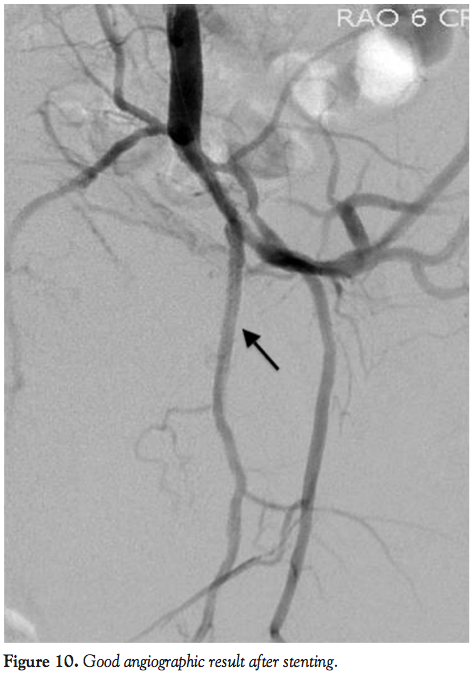

A 0.014˝, 180 cm coronary wire was used to cross the lesion in the left internal pudendal artery. A 2.0 x 20 mm coronary monorail balloon was used to dilate the lesion with serial inflations to 10 atm. Angiography following balloon dilation demonstrated a suboptimal result with dissection of the artery (Figure 9). A 2.5 x 28 mm coronary drug-eluting stent was positioned in the distal aspect of the lesion and deployed at 10 atm. Another 2.5 x 12 mm coronary drug-eluting stent was positioned in the proximal aspect of the lesion, overlapping the

previously placed stent, and deployed at 14 atm. A 2.75 x 30 mm non-compliant coronary balloon was positioned in the stented area and postdilation was performed to 18 atm. Angiography following postdilation demonstrated no residual disease in the treated segment (Figure 10). There were no complications and the patient was discharged home the same day. The patient reported significant improvement in erectile function at clinical follow-up.